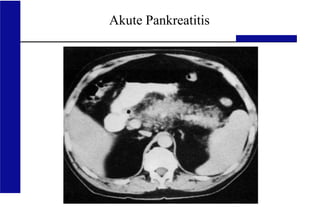

CT-Abdomen bei der schweren akuten Pankreatitis

• Bei klinischer Unsicherheit rasch und bei

fehlenden Kontraindikationen mit Kontrastmittel

(Ausschluss Perforation, Mesenterialischämie usw.)

• Wenn möglich nach Volumentherapie und nach 48-

72 h wegen besserer Darstellung der Nekrosen

CT-Befund Grad

Normales Pankreas A

Pankreasvergrößerung B

Entzündliche Veränderungen des

Pankreas und/oder des

peripankreatischen Fetts

C

Eine peripankreatische

Flüssigkeitsansammlung

D

Zwei oder mehr

Flüssigkeitsansammlungen

und/oder retroperitoneale Luft

E